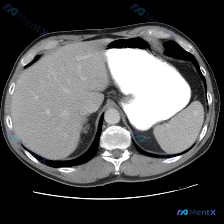

今天看到一个挺有警示意义的影像读片场景,整理一下思路: 初始问题与预设 用户直接问:「这个图像里的脾脏病变是什么异常?」 预设非常明确:先认定了存在脾脏病变,让我们找出来并定性。 影像事实(基于提供的单层面上腹部CT软组织窗横断面 1. 扫描范围:上腹部较高层面,显示部分肝脏、脾脏、腹主动脉等结构...